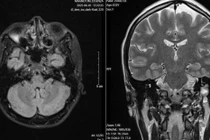

Hình ảnh chụp phim cho thấy khối u ăn mòn tiêu xương sàn ổ mắt. Ảnh nguồn tienphong.vn